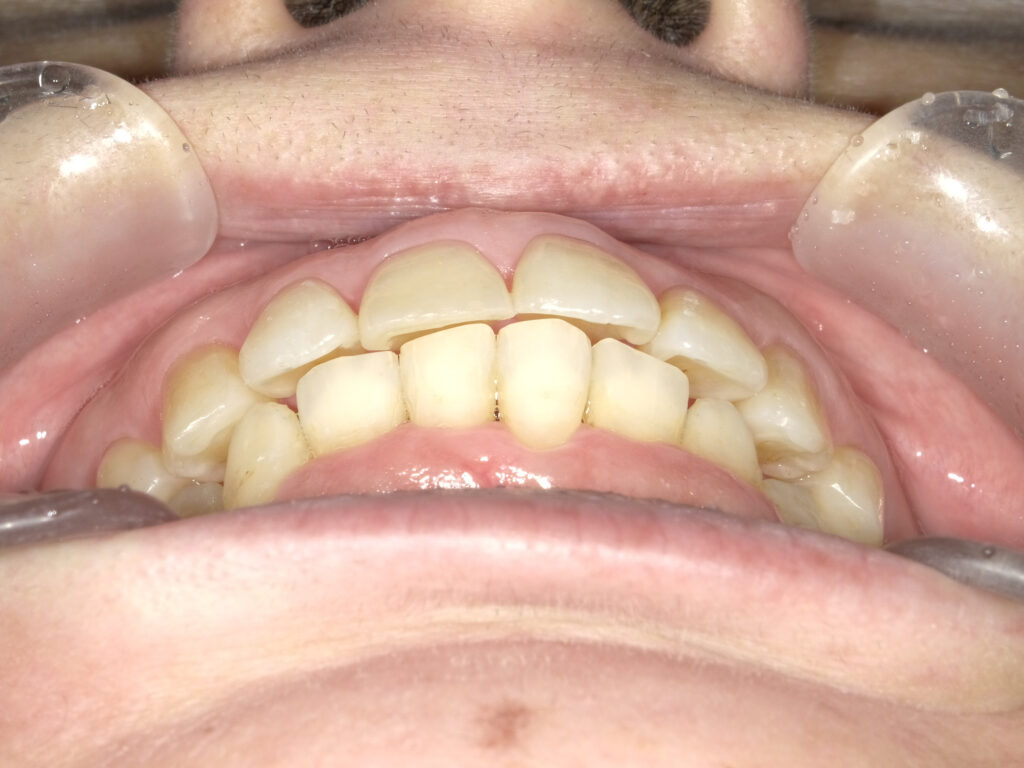

正面

治療前

患者様は左上1番の前突と、上下2番のガタつきを気にされてご来院されました。 IPRによりわずかなスペースを確保し、前歯を約1mm後退させることで前突感を改善した。 |